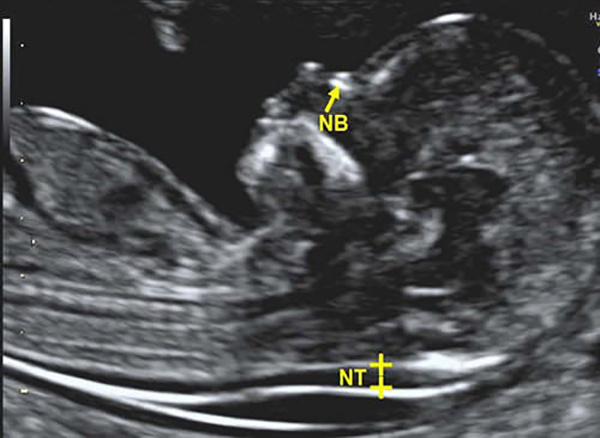

Đo độ mờ da gáy có biết trai hay gái? Để có được thông tin chính xác nhất thì trước hết bạn cần phải tìm hiểu về đo độ mờ da gáy nghĩa là như thế nào? Đây là một thuật ngữ các bác sĩ sử dụng khi siêu âm cho thai nhi và đo độ mờ ở phần da gáy của thai. Tại sao lại đo da gáy mà không phải vị trí khác? Bởi, da gáy của thai nhi luôn kết tụ những dịch của vùng cổ da mặt thai nhi. Dựa vào việc đo chỉ số mờ da gáy này mà các bác sĩ sẽ biết được nguy cơ về các dị tật bẩm sinh trong đó có hội chứng Down mà bé có thể gặp phải.

Trường hợp, khi siêu âm mà các bác sĩ đo độ mờ da gáy mà kết quả không bình thường. Lúc này các chuyên gia sẽ yêu cầu các mẹ thực hiện các xét nghiệm khác để có được kết quả chính xác nhất. Đo độ mờ da gáy của thai nhi thường được chỉ định thực hiện ở tuần thai thứ 11 đến 14 của thai kỳ. Mẹ bầu làm xét nghiệm quá sớm cũng không được vì lúc này da gáy sẽ rất mờ và không có được sự chính xác.

Khi chị em thực hiện siêu âm thì lúc này hình ảnh thai nhi sẽ được các bác sĩ phóng to. Sau khi đo các thông số cơ thể chiều dài của thai nhi thì đo độ mờ da gáy với da của bé là màu trắng và khoảng mờ đó chính là màu đen. Trường hợp các mẹ đo độ mờ da gáy của thai nhi ở tuần thứ 11 nếu chúng là khoảng 2mm thì mẹ an tâm. Còn nếu ở tuần 13 thì độ mờ da gáy đạt tiêu chuẩn là 2,8mm còn ở tuần tiếp theo thì chúng sẽ lớn hơn 3mm.